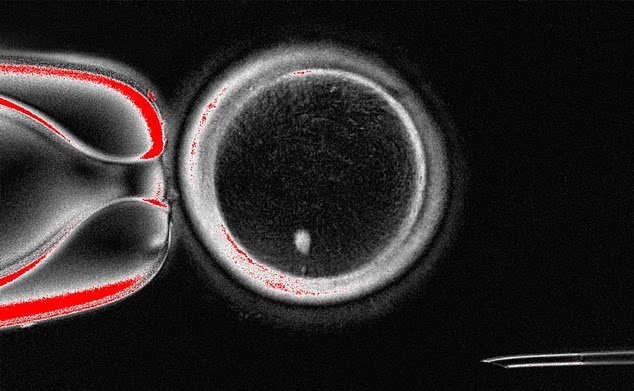

در جریان آزمایشها، محققان توانستند با استفاده از این فرآیند ۸۲ تخمک سالم را تولید کنند که سپس در آزمایشگاه بارور شدند. تقریباً ۹ درصد از این تخمکها به مرحله بلاستوسیست (مرحله خاصی از رشد جنین) رسیدند. با این حال، محققان بلاستوسیستها را پس از این مرحله کشت ندادند که این زمان مصادف با زمانی است که معمولاً در درمان IVF به رحم منتقل میشوند.

با وجود اینکه این یافتهها امید تازهای به زنانی میدهد که مشکلات تخمک دارند تا بتوانند فرزندانی با ژنتیک خودشان داشته باشند، اما کارشناسان به چندین نقص در این مطالعه اشاره کردهاند. نکته مهم این است که بخش عمدهای از آنها (۹۱ درصد) پس از لقاح، رشد نکرده و متوقف شدند. علاوه بر این، در تعدادی از بلاستوسیستها اختلالات کروموزومی مشاهده شد.